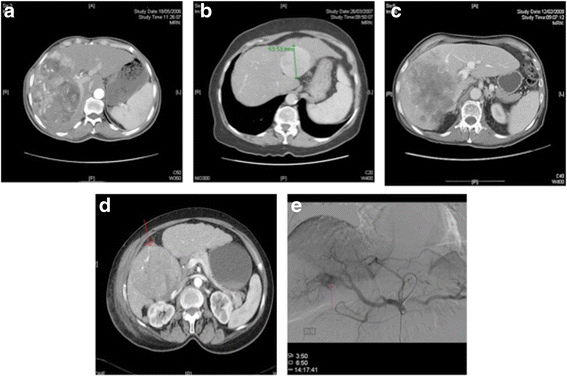

Results: Median OS was 15.4 months. Tumour size > 7 cm (p < 0.001), intra-tumour necrosis (ITN) (p = 0.02) and arterial ectatic neovascularisation (AEN) (p = 0.03) emerged as individual prognostic factors together with radiologic response (p < 0.001) and elevated alpha-fetoprotein (AFP) (p = 0.01). Combination of tumour size > 7 cm, ITN and AEN identified patients with poor prognosis (p < 0.001).

Conclusions: We identified a coherent signature based on commonly available imaging biomarkers likely to be reflective of differential patterns of relative hypoxia and neovascularisation. Large tumours displaying AEN and ITN are characterised by a shorter survival after TACE.